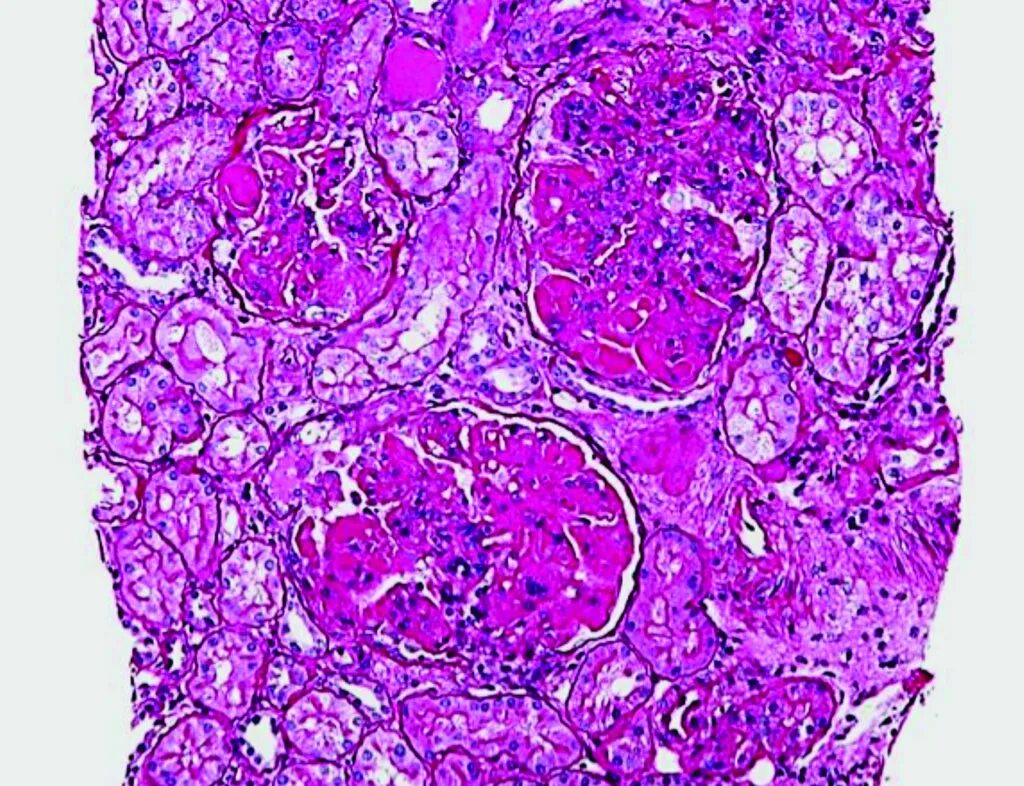

Гистологическое исследование почек